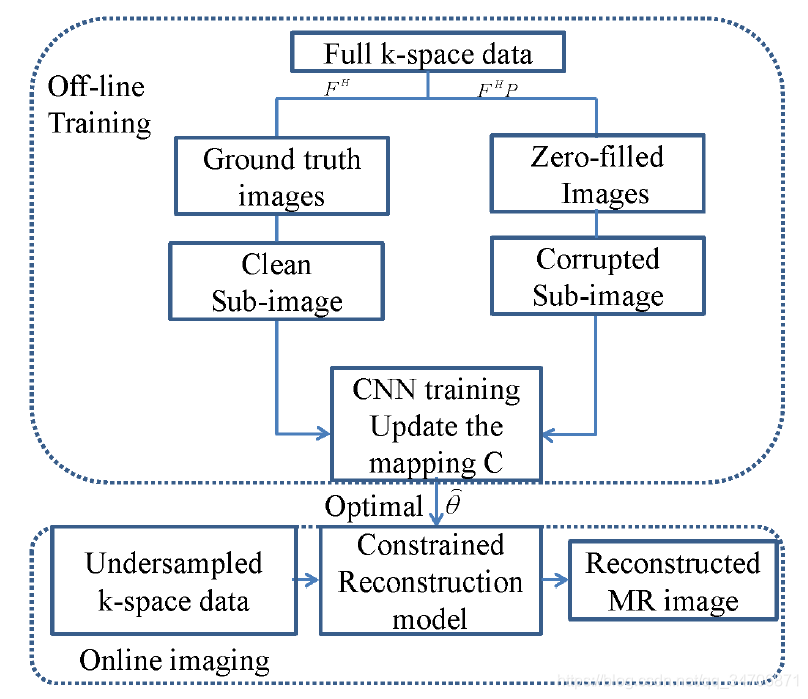

近年来,随着深度学习的火热,MRI的重建也有了很多基于深度学习方法,如图5所示的网络模型【2】。由于MRI采集的数据是在复数域的,因此直接传到处于实数域的神经网络上肯定不行,一般有两种解决方法,(1)只取MRI数据的实部或者幅度,这样MRI数据就变成了实数。(2)网络的输入是 two channels,分别存MRI的实部和虚部。

传统方法相对于神经网络的方法而言,是比较难一点的,因为我们需要根据先验信息列出一个优化问题,再通过迭代的方法去求解这个问题,基本不需要或只需要非常少的训练数据。而基于神经网络的方法,不需要我们去求解这个优化问题,我们只需要根据先验信息设计出相应的网络结构,它就会根据大量的训练数据和通用的机器学习算法学到很不错的网络参数。

传统方法比较难,但目的明确;深度学习方法相对简单,但比较虚(心虚)。将传统方法和深度学习方法结合起来也是一个比较好的思路。